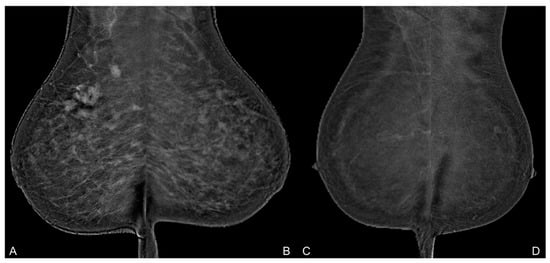

- Meucci, R.; Pistolese, C.A.; Perretta, T.; Vanni, G.; Beninati, E.; Di Tosto, F.; Serio, M.L.; Caliandro, A.; Materazzo, M.; Pellicciaro, M.; et al. Background Parenchymal Enhancement in Contrast-enhanced Spectral Mammography: A Retrospective Analysis and a Pictorial Review of Clinical Cases. In Vivo 2022, 36, 853–858. [Google Scholar] [CrossRef]